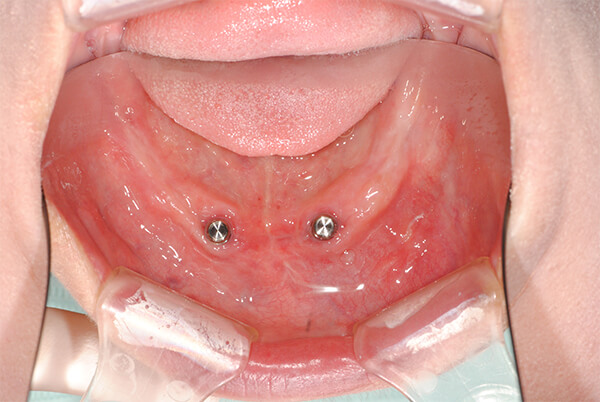

インプラントオーバーデンチャー(IOD)

インプラントオーバーデンチャー(IOD)とは

インプラントオーバーデンチャーとは、総入れ歯を使用中の場合や、全ての歯を失ってしまった場合のように、総入れ歯をインプラントで固定して使用する治療法です。歯が1本もないという方に2~4本程度のインプラントを顎の骨に埋入し、入れ歯(義歯)をインプラントで固定する治療法です。

1.インプラント固定式入れ歯(義歯) 2本

食事中、下アゴの入れ歯が動いて痛い、もっとよく咬めるようにしたい方。たった2本のインプラントで下アゴの入れ歯の動きを抑え安定させる治療で入れ歯はとても快適なものになります。

現在使用中の入れ歯がそのまま使える可能性もあり、費用を抑えたい方や、外科的侵襲を最小限にしたい場合等、多くのメリットがある方法です。

インプラントオーバーデンチャー、2-IODとも言われています。

治療の流れ

① 前歯部に埋入されたインプラント。この部位は大きな脈管もなく、かなり骨吸収が進んでいてもインプラントの埋入が可能です

② 口腔内に装着されたアタッチメントのメール部